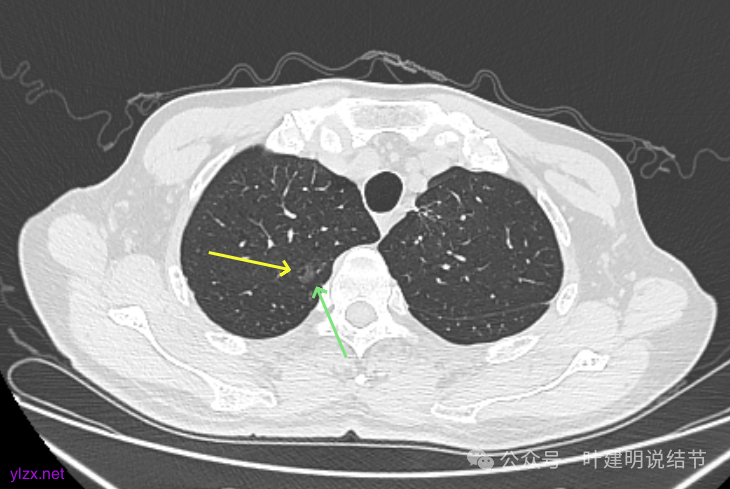

再看2022年9月的:

右上病灶此层面偏长条,密度较低。

左上已经手术。

左上另有一处磨玻璃结节,由于手术后结构变化,此灶是术前哪处感觉不太好对比。